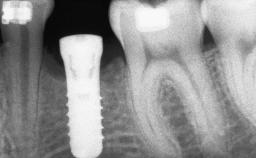

# of Teeth 1

# of Implants 1

Type of Implants Two-Piece